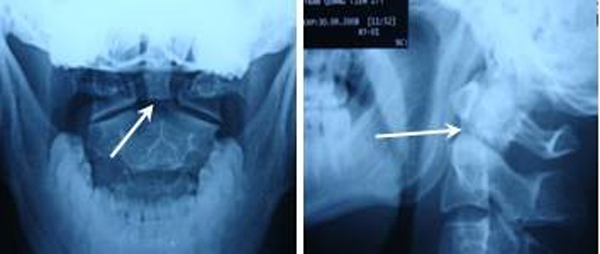

Chẩn đoán hình ảnh: Tất cả bệnh nhân được chụp X Quang quy ước (thẳng, nghiêng, há miệng) và cắt lớp vi tính 64 dãy có dựng hình đánh giá vị trí đường gãy, tình trạng khớp đội – trục bên, khoảng cách di lệch mỏm nha so với thân C2. Chụp cộng hưởng từ phát hiện tổn thương tủy và tình trạng dây chằng ngang.

Tuổi trung bình 28 ± 4,69 tuổi (24 – 33), tất cả bệnh nhân đều là nam giới, nhập viện vì nguyên nhân tai nạn giao thông (1 bệnh nhân) và tai nạn ngã cao (3 bệnh nhân) với cơ chế ngã cắm đầu về phía trước. Trên lâm sàng, tất cả BN không có biểu hiện tổn thương thần kinh, VAS trung bình 6 ± 0,816 điểm (5-7). Chụp X quang quy ước và chụp cắt lớp vi tính 64 dãy dựng hình có tổn thương gãy mỏm nha loại 2.